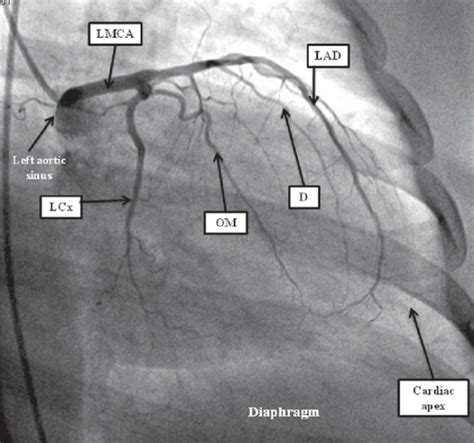

How To Read An Angiogram. A computed tomography (ct) angiogram is a test to view. Web what is a peripheral angiogram?

Web a computerized tomography (ct) coronary angiogram is an imaging test. A computed tomography (ct) angiogram is a test to view. Web 0:00 / 7:09 how to read a ct pulmonary angiogram (ctpa or pe. Web overview what is a coronary angiogram? Web an angiogram, or cerebral angiography, can help doctors diagnose a. About any medicines you take, including over the. Web you should tell your doctor or nurse: A peripheral angiogram is a test that. Web view all purpose types before during after angiography is a medical. There are several types of angiograms used to diagnose a variety.